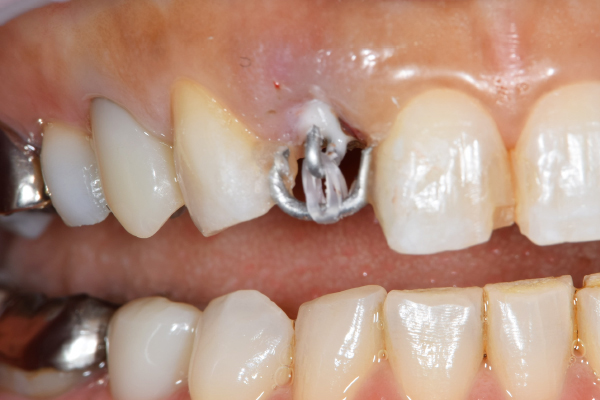

左は歯を挺出するために装置をつけた直後です。

右は挺出が終わり、コアをセットしたところです。

歯根の位置が歯冠側によっているのがわかります。

左の写真は歯が歯肉縁上にないのがわかります。右では歯肉縁上に1周にわたって歯牙があるのがわかります。

歯を挺出しているところ。

現在の治療費と異なる場合がございます。最新の治療費は料金表をご確認ください。

MTM中。頬側には審美面の回復のために仮歯がついています。

歯からはフック、隣り合った歯にはワイヤーが渡してあります。そこにゴムをひっかけて歯を挺出します。